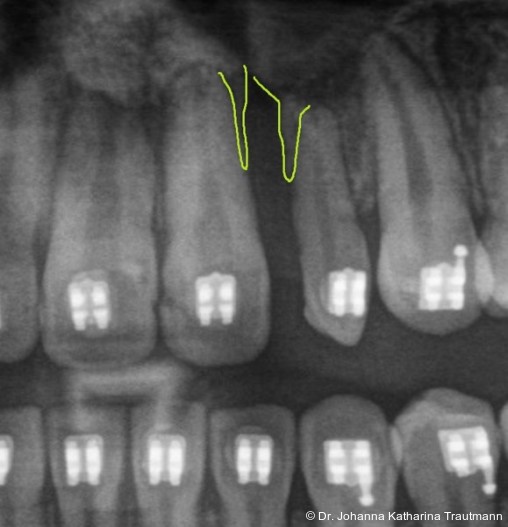

Das Fernröntgenseitenbild zeigte eine skelettale Klasse IIAnomalie mit einem Wits von 5,6 mm, bei einer tiefen Konfiguration (ML NL = 16,5°) mit bialveolär retrudierten Fronten (OK1NA = 5,9°; UK1NB = 10,4°), was sich auch in der Modellanalyse widerspiegelte. Hier zeigte sich zudem ein schmaler Oberkiefer mit multiplen Kippungen und Rotationen in der Front, einem hypoplastischem 22 sowie einer Mesialwanderung des 16. Des Weiteren zeigte sich eine asymmetrische Bisslage mit 1 PB distal rechts und ½ PB distal links bei einem Overjet von 2,5 mm sowie einem Overbite von 5 mm. Während im Unterkiefer bereits die zweite Zahnwechsel phase begonnen hatte, zeigte sich im Oberkiefer noch kein Wechsel in den Stützzonen. Gerade bei Patienten mit Spaltbildungen ist eine engmaschige Überwachung des Durchbruchs der oberen Eckzähne essenziell. Während bei der Allgemeinbevölkerung die Prävalenz von verlagerten Eckzähnen bei ca. 2,8 Prozent liegt2, ist diese bei Patienten mit Lippen-Kiefer-Gaumen-Spalten um den Faktor 10 erhöht.3, 4 Als klassische Risikofaktoren gelten zudem Platzmangel, transversale Enge aber auch Fehlstellungen, Nichtanlagen oder Hypoplasien der zweiten Schneidezähne. Diese übernehmen normalerweise die Funktion der Leitschiene für den S-förmigen Durchbruch der Eckzähne. Im vorliegenden Patientenfall kommen also mehrere Risikofaktoren für eine Verlagerung zusammen, was die rechtzeitige Diagnostik zur Abklärung einer Durchbruchsproblematik rechtfertigt. Da im Spaltbereich auch zusätzlich ein ausgeprägtes Knochendefizit vorliegen könnte, sollte auch immer die Option einer sekundären Osteoplastik abgewogen werden, deren Indikation und Timing optimal zum Durchbruch der Canini angepasst werden sollte.5

Zur genaueren Diagnostik der Lage beziehungen der Eckzähne und des Knochenangebotes im Spaltbereich kann neben den kieferorthopädi schen diagnostischen Unterlagen laut der S2 kLeitlinie Dentale digitale Volumentomografie6 auf eine dreidimensionale Bild gebung zurückgegriffen werden. In dieser zeigte sich eine vestibuläre Verlagerung des 13, eine palatinale Verlagerung des 23, sowie ein deutliches Knochendefizit im Spaltbereich mesial des hypoplastischen 22 (Abb. 2). Nach Auswertung der 3D-Daten erschien aufgrund der palatinalen Lage des 23 eine invasive Operation wie eine sekundäre Osteoplastik keinen entscheidenden Vorteil für die weitere Be handlung zu haben. In Rücksprache mit der Mund-Kiefer-Gesichtschirurgie der UMG wurde daher auf die OP verzichtet und initial die kieferorthopädische Therapie in den Vordergrund gestellt.